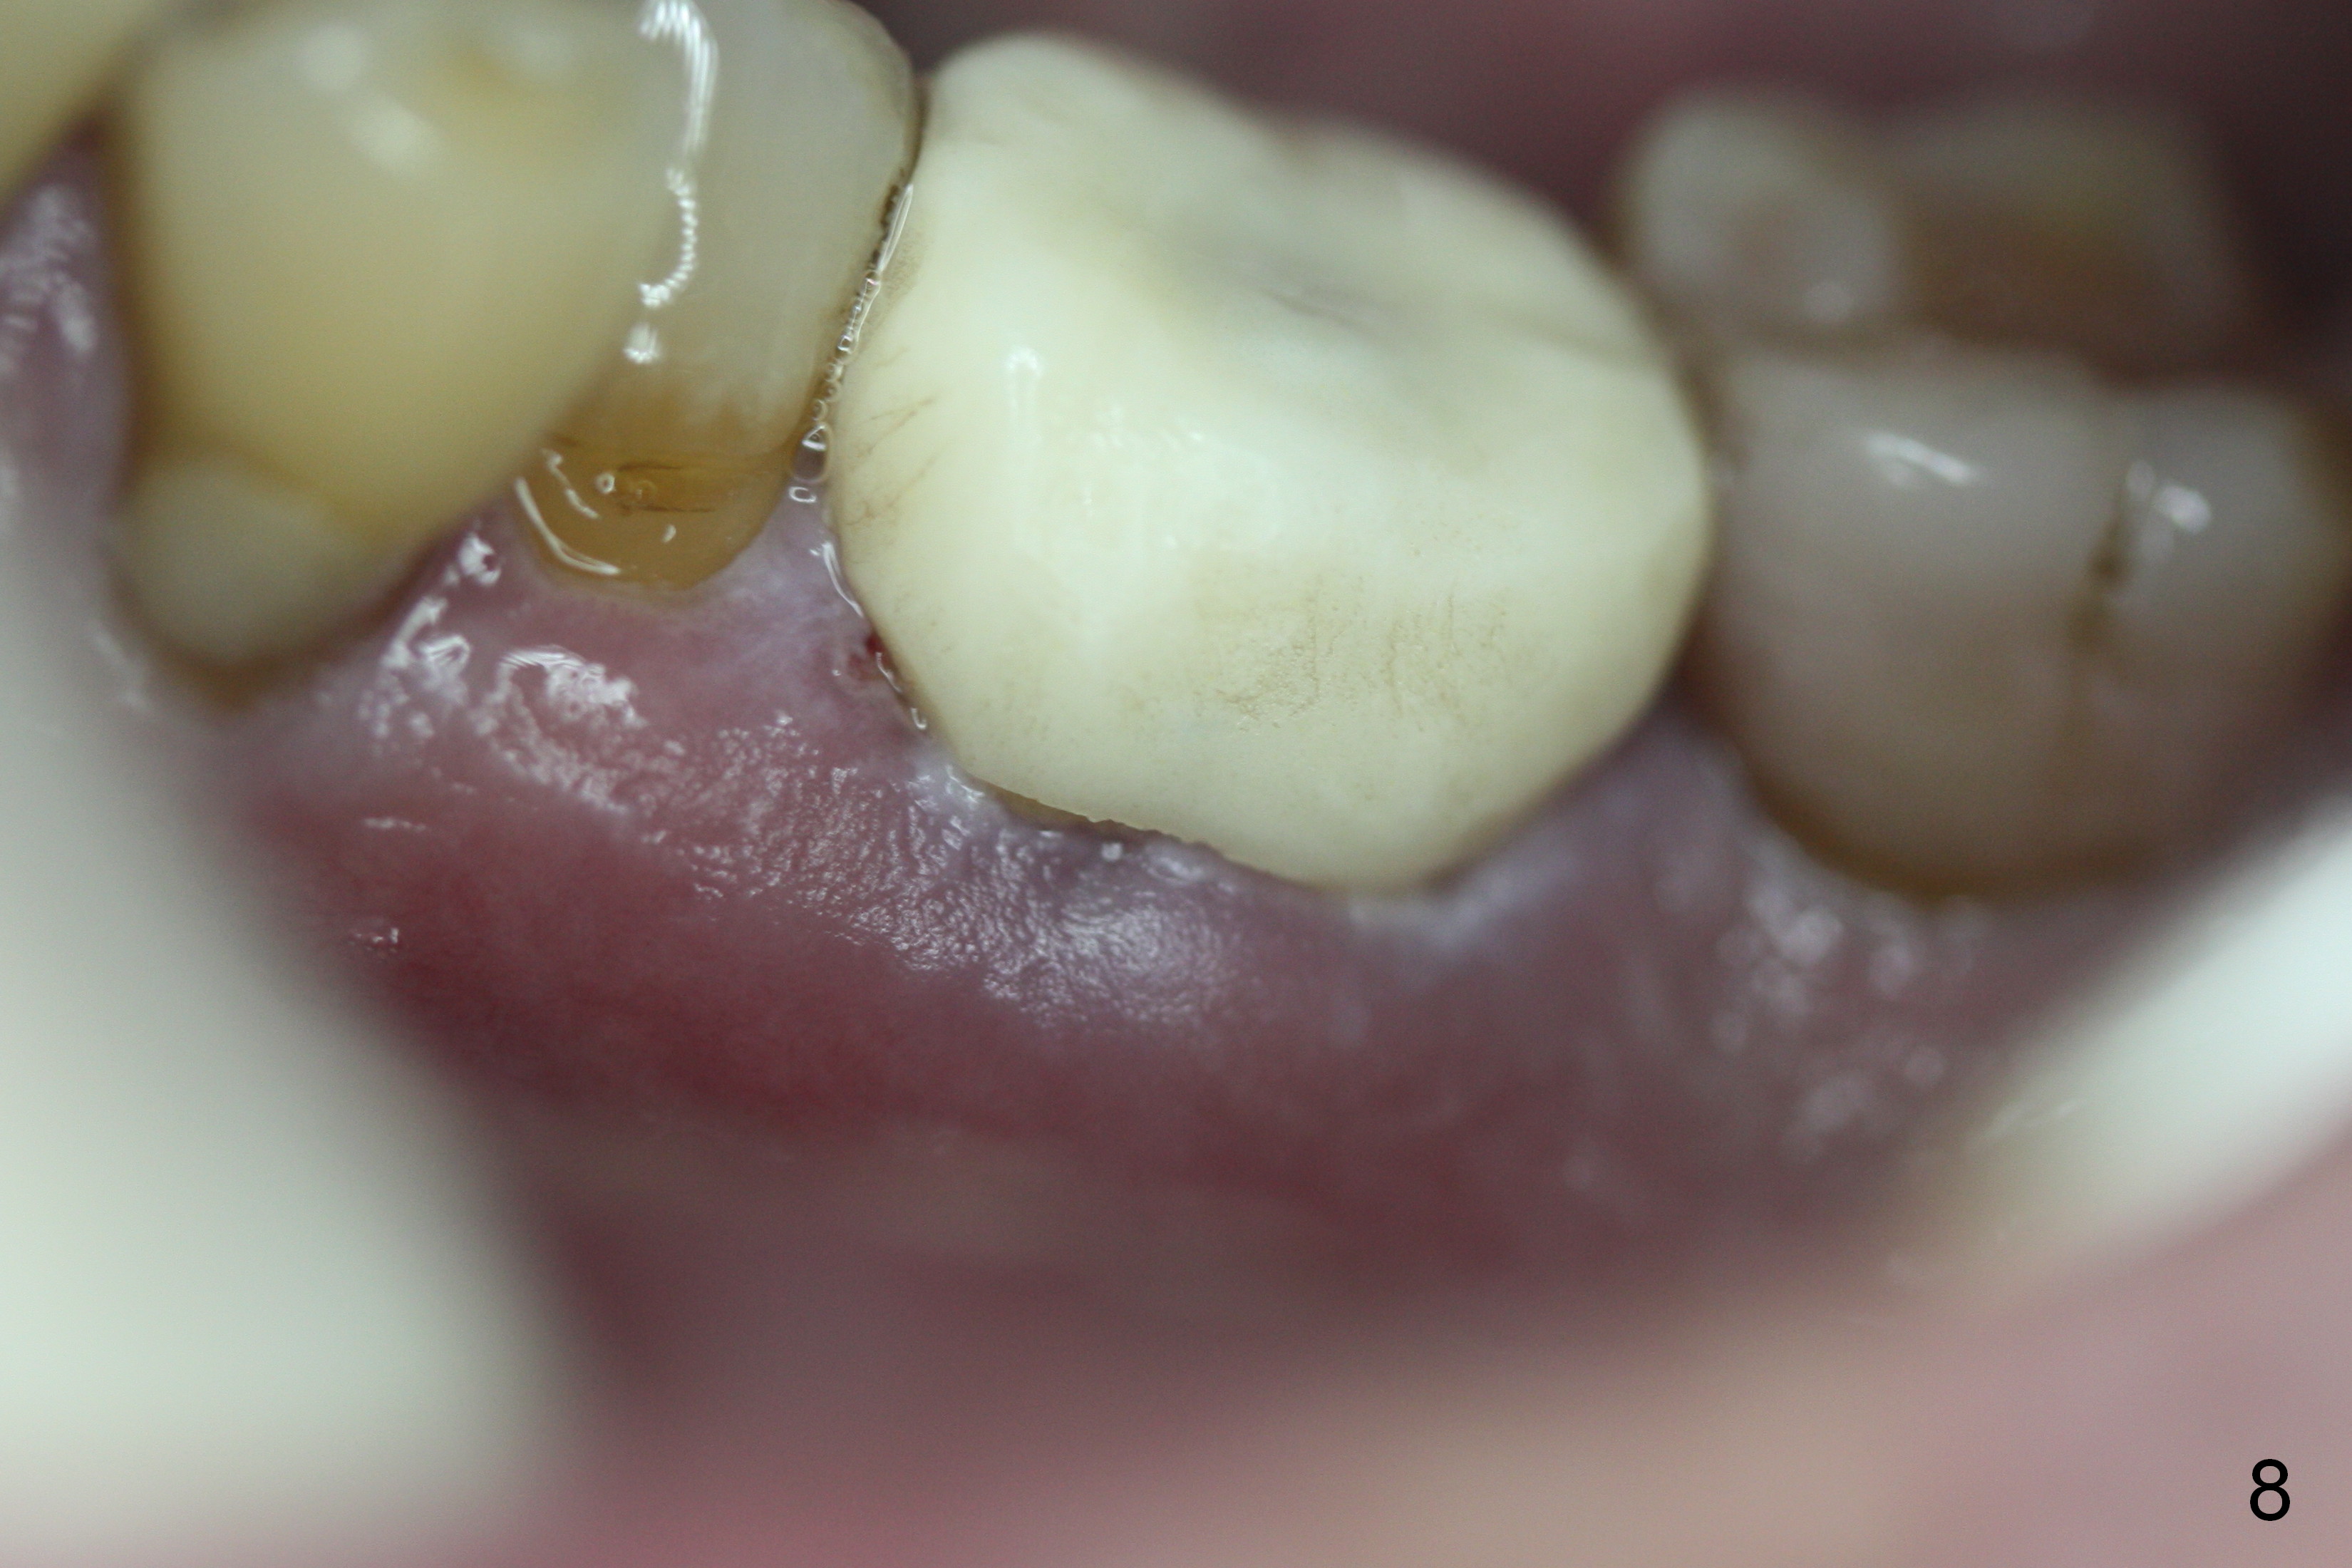

The patient remains asymptomatic 6 days postop (Fig.8,9). The fistula is resolving (Fig.9 <). The provisional is removed for reline.